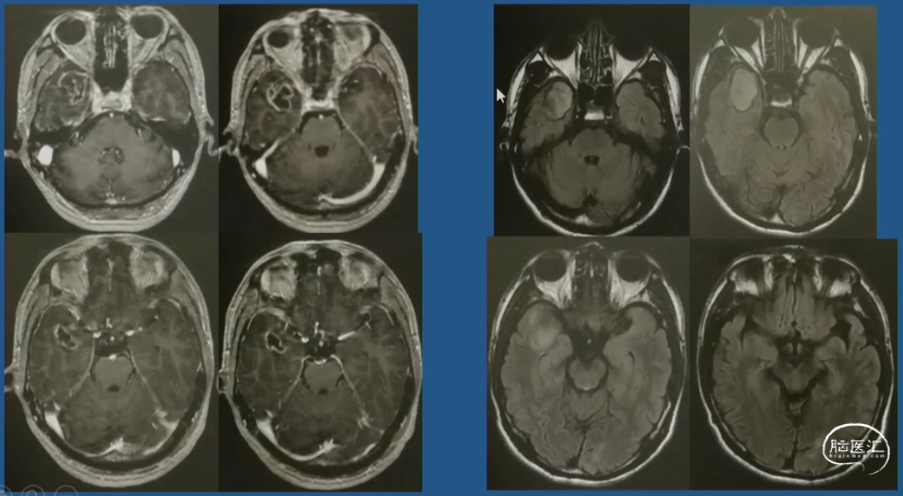

术前影像

术后影像(术后两年)

病例示例2 右侧岛叶占位-病史

术前影像

术后三年影像-肿瘤控制良好